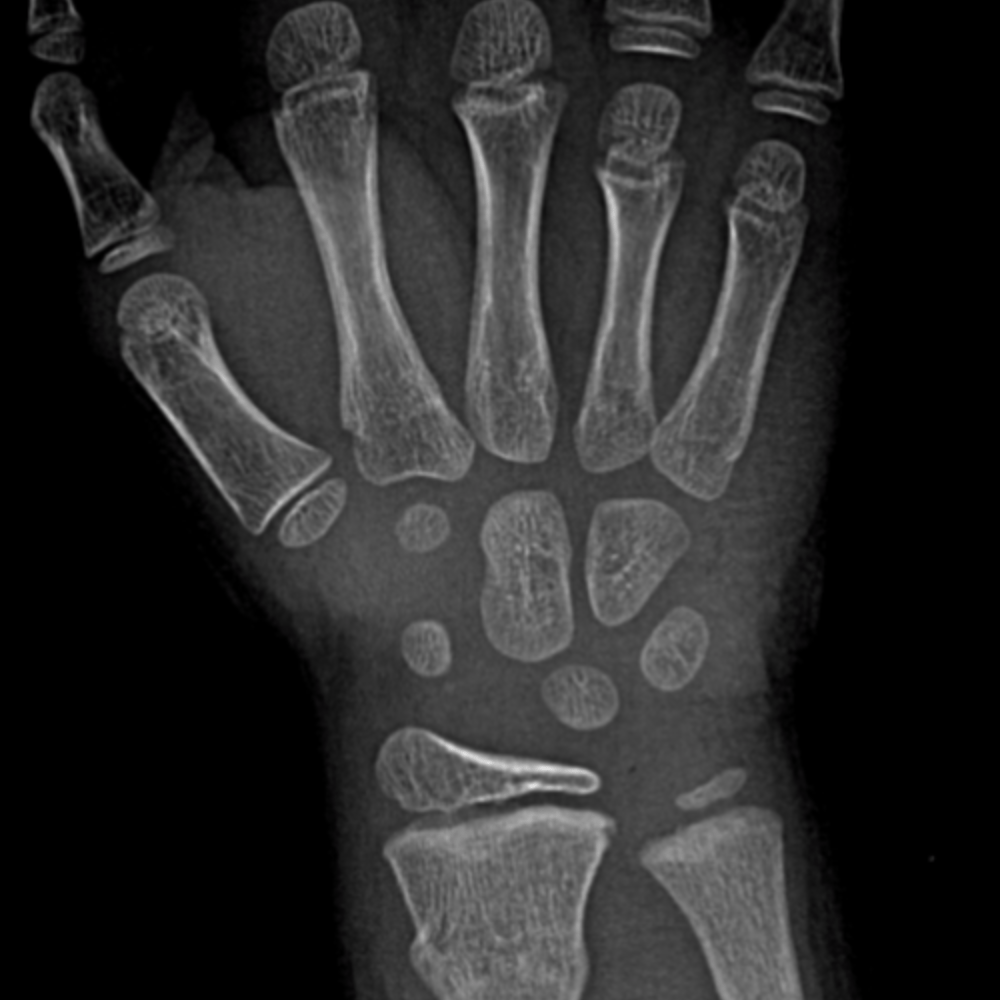

CaseStacks.com - Free Case #1

CaseStacks.com - Free Case #1 www.casestacks.com

pediatric radiograph casestacks peds